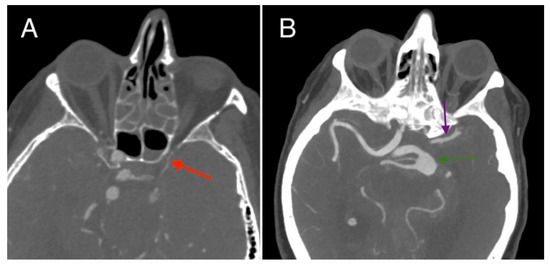

2. Case Report